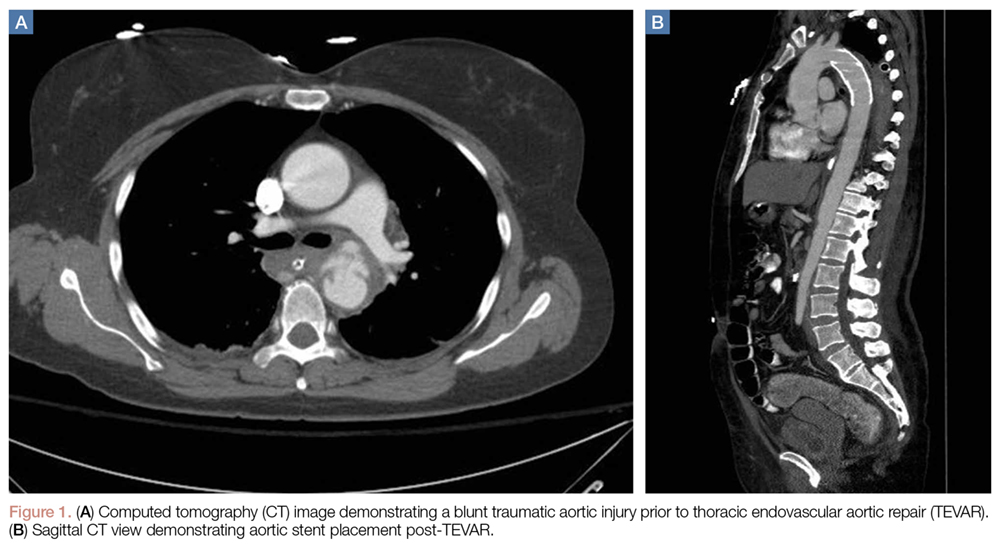

Thoracic endovascular aortic repair (TEVAR) for blunt thoracic aortic injury has essentially replaced open surgical repair. (See Figures 1a and 1b for an example of a blunt traumatic aortic injury prior to and post-TEVAR placement.)

While TEVAR has demonstrated decreased mortality, hospital length of stay, and procedure-related paraplegia when compared to open repair,40,41 the rate of graft-related complications, has significantly increased. However, given that TEVAR is still a relatively new technique, long-term data are lacking.41Transarterial Catheter Embolization